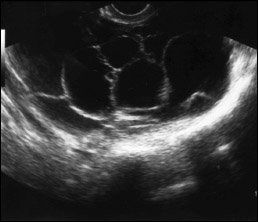

Ultrasound images of a single thin septated cyst (top); a single thick septated cyst (middle); and multiple septated cysts (bottom). Image courtesy of Edward J. Pavlik, director of research in gynecologic oncology, UK Ovarian Screening Research Program.

There were no statistical differences between the women who had tumors removed and those who did not. The only differences were the removal group had tumors greater than approximately 5 cm, and they had multiple septations, according to Dr. Saunders (2010 Society of Gynecologic Oncologists abstract 53).